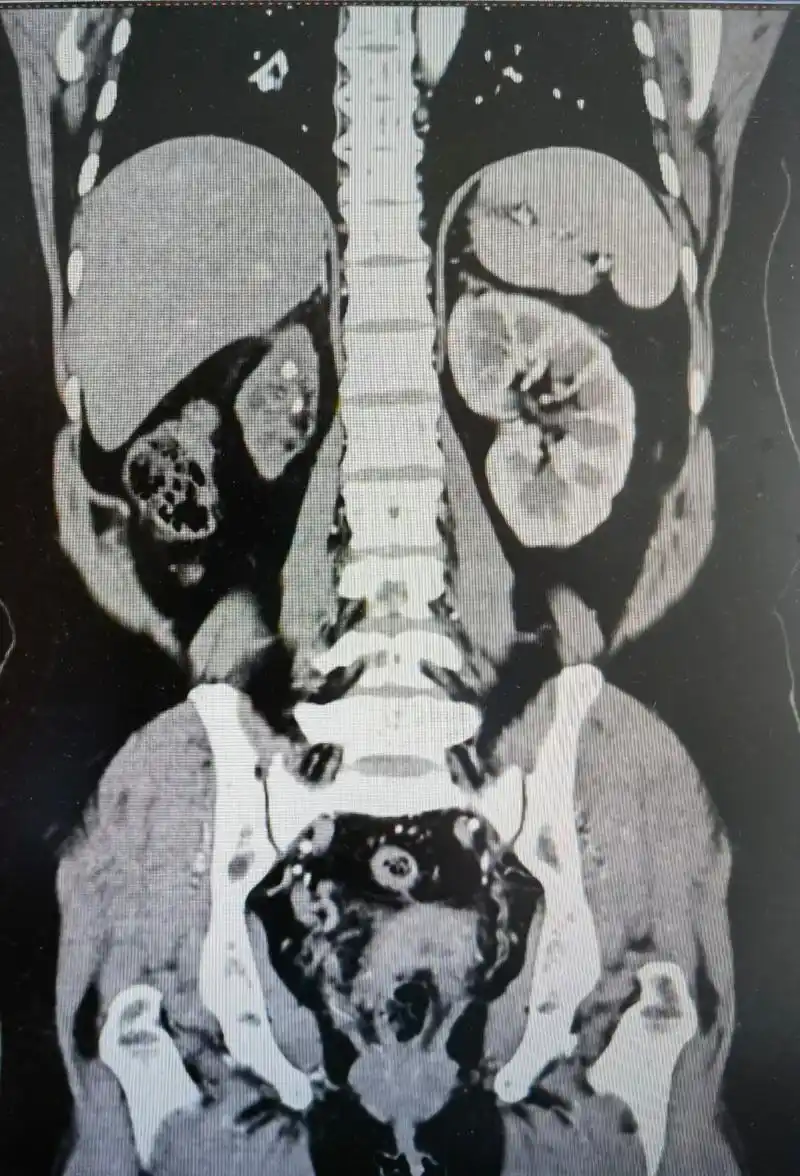

肾积水

输尿管结石致重度肾积水,反复感染,肾失功,后腹腔镜无功能肾切除,难度

双侧肾盂输尿管重复畸形并肾积水1例

原创独肾伴重度肾积水